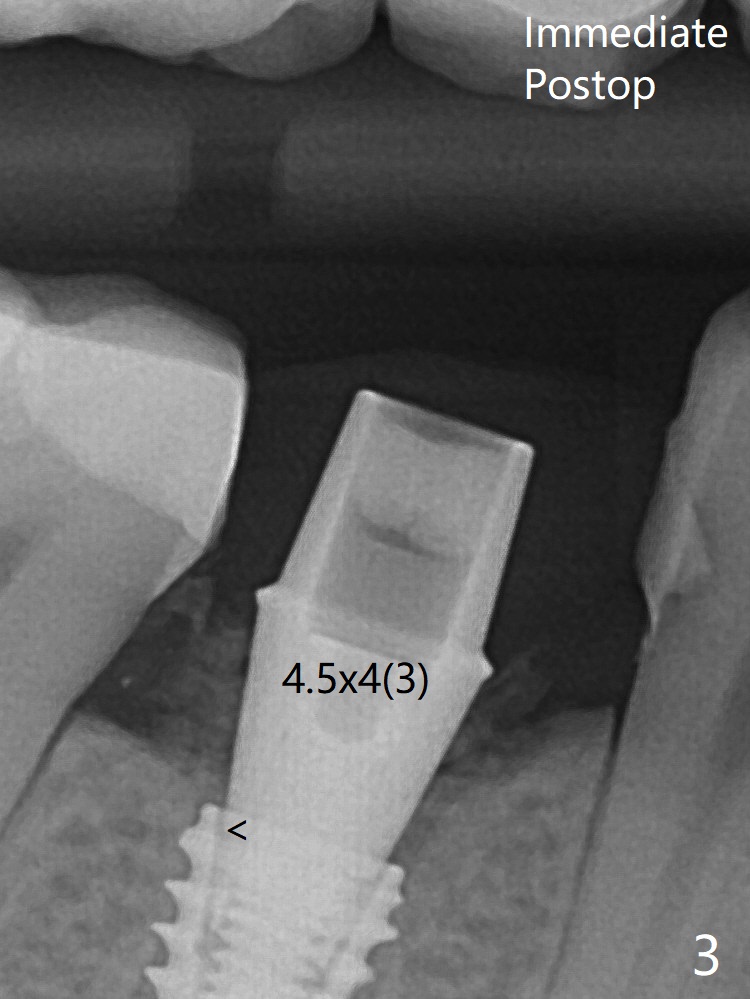

In fact a 4.5x4(3) mm cemented abutment is incompletely seated with a gap (<), probably due to interference from the mesial crest. A profile drill should have been used. There is foul smell from the immediate provisional; in fact it may be due to the loose contact between the implant and abutment (Fig.4 < (4 months postop)). The gingiva is unhealthy. A 5.5x5 mm healing abutment is placed.